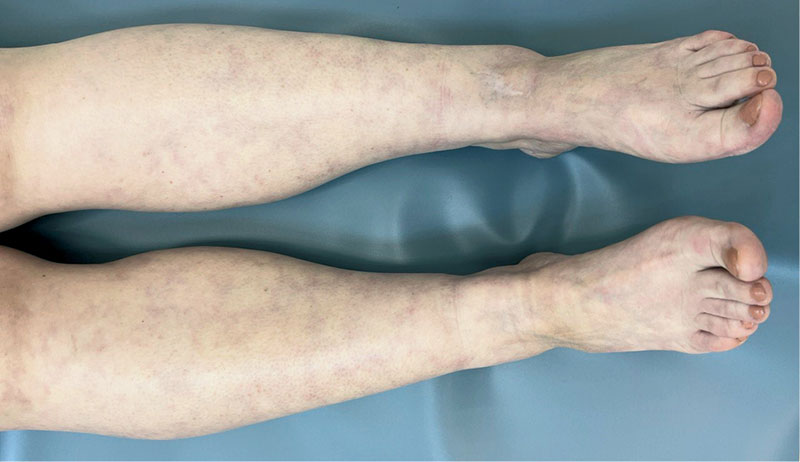

Рис. 7. Пациентка с ЛВ без язв после проведения комплексной терапии с применением НТАП

В обеих группах после проведенного лечения наблюдалась положительная динамика в виде исчезновения онемения и боли в нижних конечностях, активации заживления язвенных дефектов, уменьшения выраженности ливедо, но при присоединении к основной терапии процедур низкотемпературной аргоновой плазмы наблюдалось более выраженное улучшение со стороны кожного процесса у пациентов группы исследования по сравнению с группой контроля (рис. 4–14).